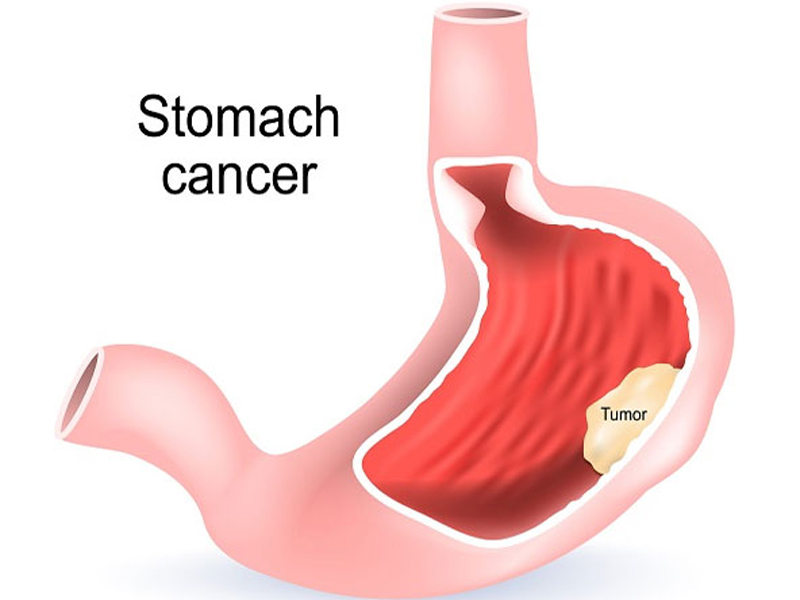

GI and Min Access Surgery

Laparoscopic Surgery

The process takes its name from the laparoscope, a slender tool that has a tiny video camera and light on the end. When a surgeon inserts it through a...